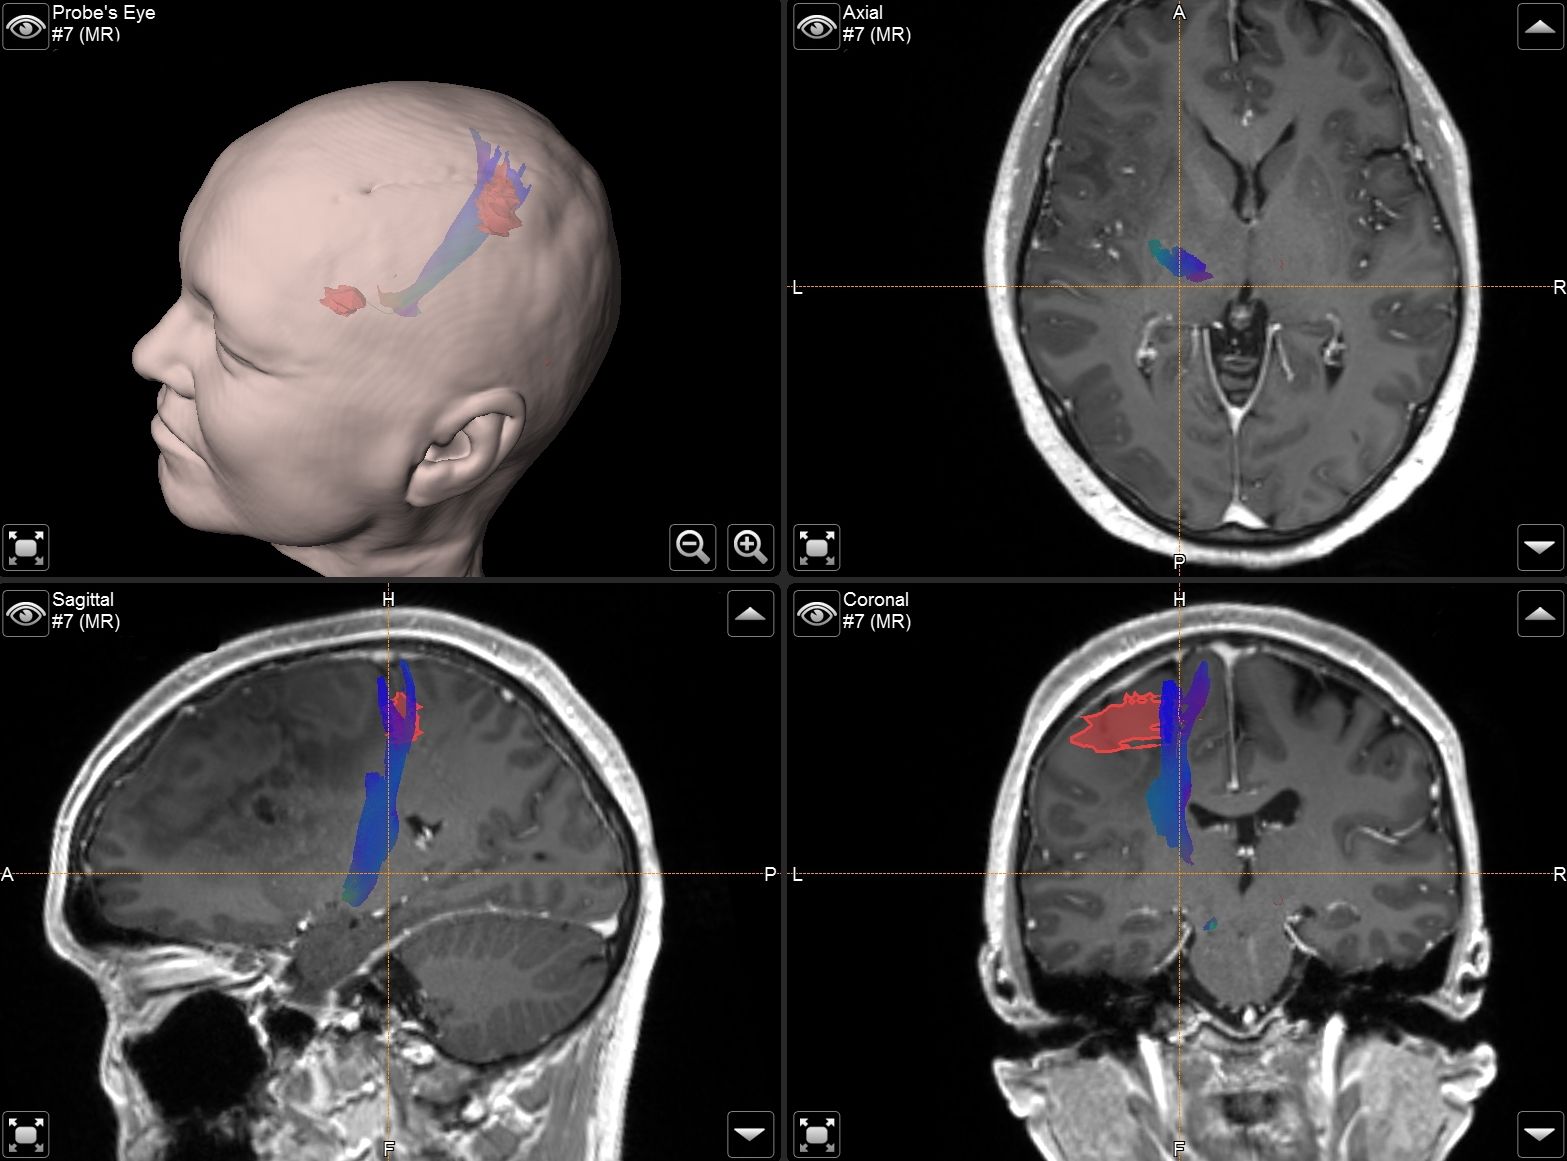

Intraoperatives MRT (iMRT)

Seit 2011 setzt die Neurochirurgie Tübingen in enger Zusammenarbeit mit der Neuroradiologie Europas erstes deckenmontiertes, bewegliches 1,5-Tesla-iMRT-System ein. Dieses hochmoderne System ermöglicht es, das an der Decke montierte 1,5-T-Hochfeld-MRT bei Bedarf direkt in den Operationssaal zu verfahren, um intraoperative Kernspinaufnahmen zu erstellen. Das intraoperative MRT kommt insbesondere bei Operationen von hirneigenen Tumoren, Epilepsieeingriffen, Eingriffen an der Hirnanhangsdrüse sowie bei Tumoroperationen im Kindesalter zum Einsatz.

Dank des intraoperativen MRTs kann das Ausmaß der Tumorresektion während der Operation überprüft und, falls erforderlich, verbleibendes Tumorgewebe sofort entfernt werden. Dies führt in vielen Fällen zu deutlich verbesserten chirurgischen Ergebnissen für die Patientinnen und Patienten.

Durch die Verwendung der Hochfeld-Technologie können zudem komplexe MRT-Sequenzen wie MR-Perfusion, Diffusions-Tensor-Bildgebung (DTI), Spektroskopie und sogar funktionelle Analysen durchgeführt werden. Auf diese Weise ermöglicht das intraoperative MRT eine optimale neurochirurgische Tumorresektion bei gleichzeitiger Minimierung des Risikos für neurologische Ausfälle